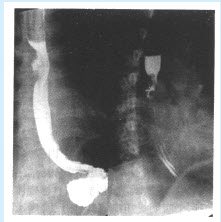

患者,男,65岁。出现进行性吞咽困难,偶出现胸骨后疼痛。行食管吞钡检查如图。

(单选题)该患者首先考虑()

A:食管异物

B:食管贲门失弛缓症

C:食管癌

D:食管平滑肌瘤

E:食管静脉曲张

F:以上都不是

第2题,共4个问题

(单选题)该病好发于()

A:食管入口处

B:食管上段

C:上段与中段交界区

D:食管中下段

E:与贲门交界处

F:以上均不是

第3题,共4个问题

(多选题)该病在以下分型中恶性程度最高的类型是()

A:增生型

B:髓质型

C:溃疡型

D:硬化型

E:缩窄型

F:蕈伞型

第4题,共4个问题

(多选题)该病的基本X线征象包括()

A:管腔狭窄,钡剂分流

B:黏膜皱襞消失、中断、破坏

C:管壁蠕动不对称或消失

D:管腔内不规则的充盈缺损

E:轮廓不规则的较大龛影,其长径与食管纵轴一致

F:纵隔内的软组织肿块